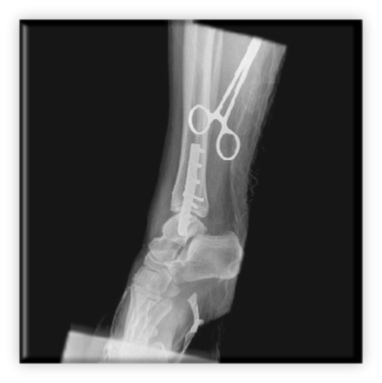

Κάταγμα κάτω πέρατος περόνης (έξω σφυρού) παρεκτοπισθέν με ταυτόχρονη παρεκτόπιση προς τα έξω του αστραγάλου. Αντιμετωπίστηκε με ανοικτή ανάταξη και εσωτερική οστεοσύνθεση με πλάκα – βίδες και μία διακαταγματική βίδα συμπίεσης

ΚΑΤΑΓΜΑ ΕΞΩ ΣΦΥΡΟΥ ΑΝΤΙΜΕΤΩΠΙΣΘΕΝ ΣΕ ΧΕΙΡΟΥΡΓΕΙΟ ΜΑΧΗΣ ΣΤΟ ΑΦΓΑΝΙΣΤΑΝ ΑΠΟ ΤΗΝ ΕΛΛΗΝΙΚΗ ΑΠΟΣΤΟΛΗ 10. Ποδοκνημική - Άκρος πόδας Αρχική σελίδα 10. Ποδοκνημική - Άκρος πόδας Ορθοπαιδικές Παθήσεις 2. Ώμος 1. Αυχένας 3. Αγκώνας 5. Σπονδυλική στήλη 6. Ισχίο 7. Μηρός 8. Γόνατο 9. Κνήμη 10. Ποδοκνημική - Άκρος πόδας 4. Άκρα χείρα - Πηχεοκαρπική